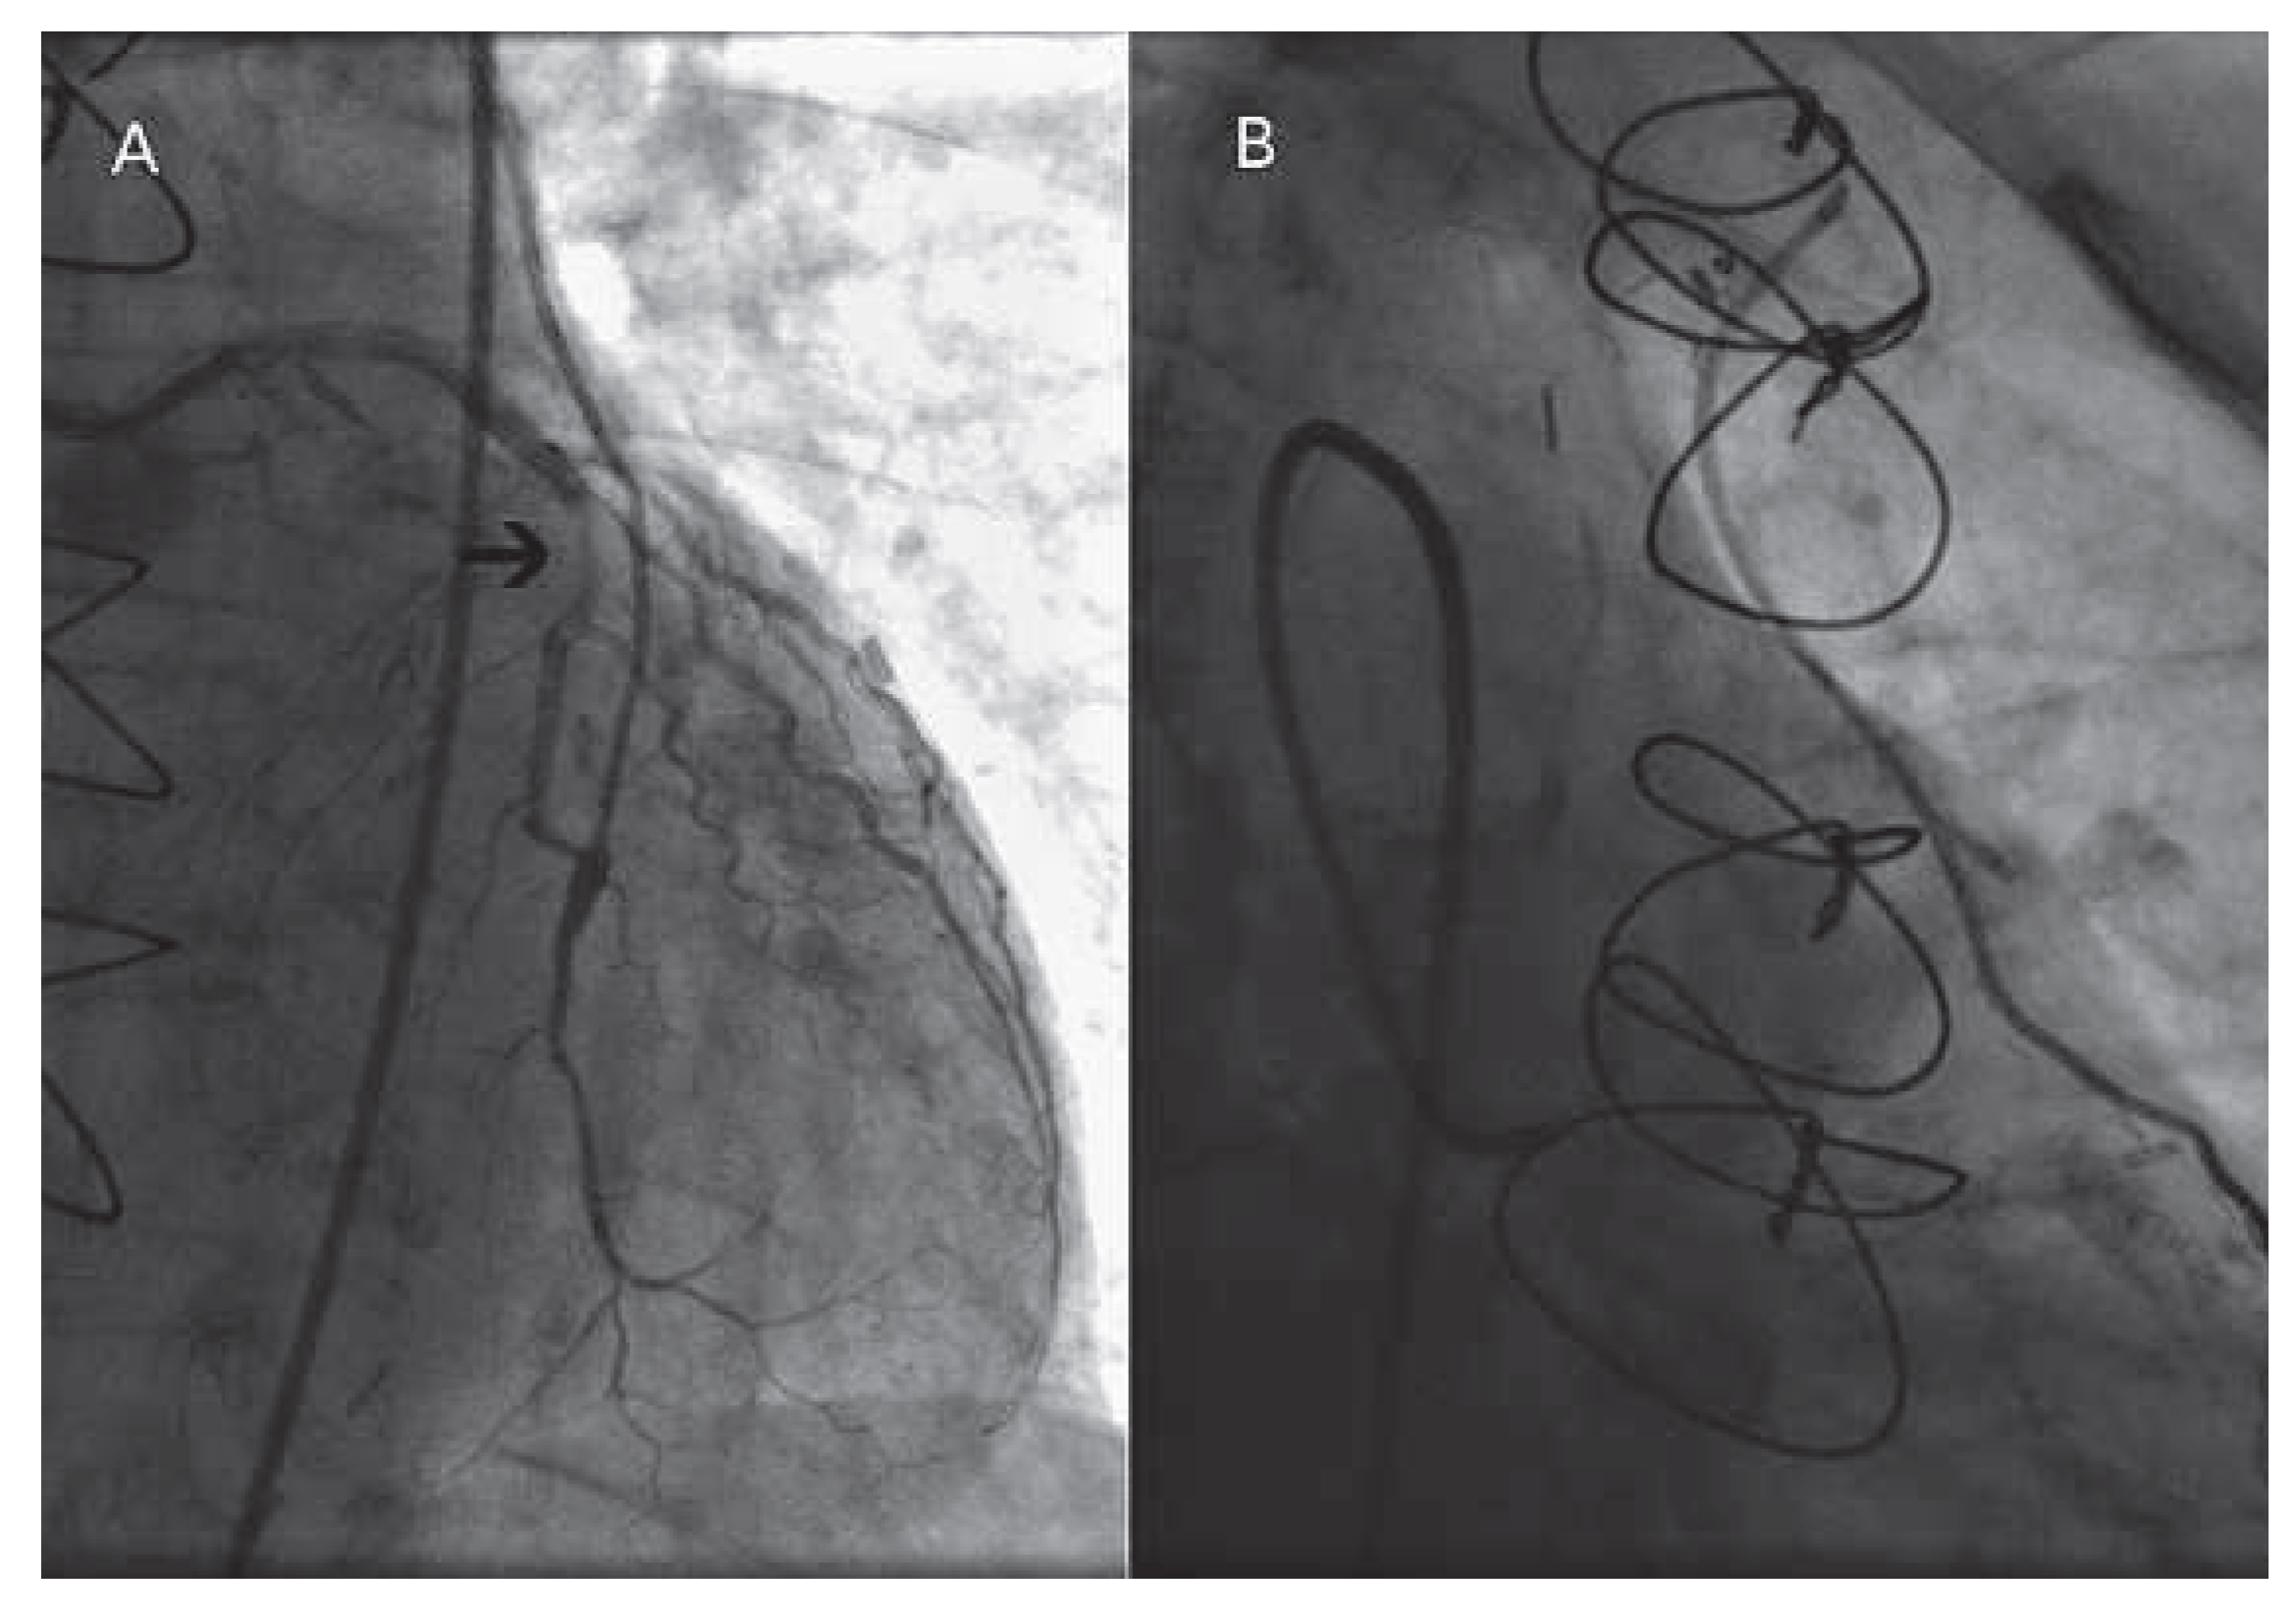

Coronary angiography showed no significant changes compared to the previous exam; all bypass grafts were patent. However, injection of contrast medium into the left main (LM) coronary artery revealed a reverse flow of blood in the left ITA throughout the cardiac cycle, consistent with a coronary steal phenomenon (Figure 1). Even at selective injection into the left ITA, an anomalously competing flow was observed in the bypass graft (Figure 2A,B). Of note, no pressure damping occurred at the intubation of the bypass graft, which rendered the presence of a significant ostial narrowing unlikely.

Figure 1. Reverse flow in the left ITA bypass, visualised at the first selective injection into the LM coronary artery; the black arrow indicates the stenosis (A). Visualisation of the complete left ITA bypass graft from its anastomosis with the mid LAD coronary artery to the left subclavian artery, after selective injection into the LM coronary artery (B).